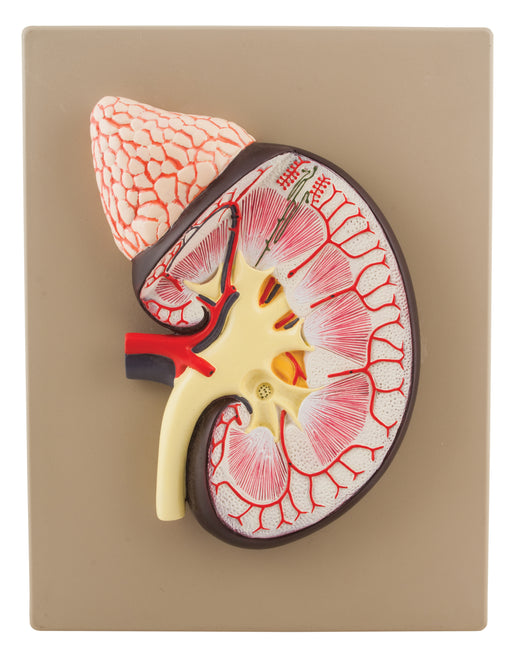

Human Kidney with Adrenal Gland Model - 3X Life Size

Kidney and Andrenal Gland is magnified 3X and cross-sectioned for in-depth study of internal structures Included key card identifies over 20 label...

View full detailsAM16060 -